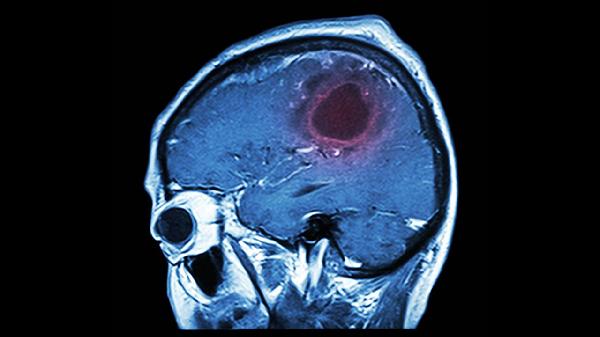

脑血栓片确实具有活血作用。该药物主要用于改善血液循环,预防和治疗血栓形成。遵医嘱使用脑血栓片有助于缓解因血瘀引起的相关症状。